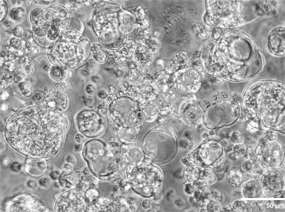

在肿瘤相关领域,赛箔与合作者共同研发基于生物3D打印技术构建的肿瘤微组织(PDT),涵盖十余个癌种,包括高发肿瘤、难治肿瘤、妇科肿瘤和儿童肿瘤,培养成功率超过了90%。通过近千例样本研究,证实PDT与患者组织具有高度一致的分子特征和药物敏感性,1-2周即可获得准确的药敏检测结果,为治疗赢取宝贵时间,并且可为新药研发企业提供药效评价、入组标准建立、适应症筛选等服务。在再生相关领域,赛箔已建立多种3D组织工程皮肤,包括表皮模型、全层皮肤模型、黑素皮肤模型等,并相应开发多种体外功效测试方法。

肺癌

宫颈癌

结直肠癌

卵巢癌

脑胶质瘤

神经母细胞瘤